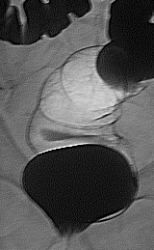

Чудесное двойное контрастирование. Дивертикулез нисходящей ободочной кишки.Кровотечение из дивертикула рядовое явление. Вопрос - почему нет снимка с двойным контрастированием слепой кишки, а только снимки с тугим выполнением?

А Вас не смущает задняя стенка, ампулярного отдела, прямой кишки?

Похоже на небольшой дефект с неровными контурами...неужели "малый" рак? Дело в том, что при попытке увеличения Ваших снимков их размер практически не изменяеется...дивертикулы то видны хорошо, а вот с прямой кишкой я "промахнулся", может сделать размер чуть больше.... Что касаемо латероскопа, то совсем не обязательно...у меня его тоже нет, неужели смена положений живот-спина и чуть косые проекции тут нам не помогут получить желаемое двойное контрастирование, опять же - опустите чуть головной конец стола...

Похоже на небольшой дефект с неровными контурами...неужели "малый" рак? Дело в том, что при попытке увеличения Ваших снимков их размер практически не изменяеется...дивертикулы то видны хорошо, а вот с прямой кишкой я "промахнулся", может сделать размер чуть больше...

Вы правы!!! Рак прямой кишки, малая форма.

Здравствуйте Анатолий Владимирович, вообще мой учитель, отмечал настороженность на ректо-сигмоидный отдел прямой кишки, на углы(печеночный, селезеночный) и восходящий отдел ободочной кишки, об этом всегда помню и делаю снимки прицельные с предворительным вывидением на контуры, в продемонстрированном случае органической патологии прямой кишки и видимого дивертикулеза больше ни чего не визуализируется. Данный случай тоже не просто так выложил, малая форма очень редко встречается, обычно когда уже всё запущено или приличных размеров.